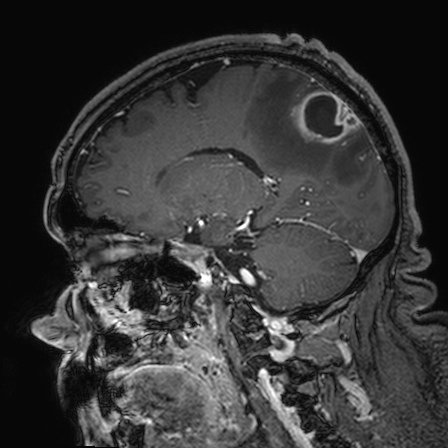

Caso neurorradiología

Paciente de 60 años con cuadro de 1 semana de evolución consistente en tropiezos frecuentes y alteración en la movilidad del miembro

inferior derecho. No refiere

cefalea u otros síntomas asociados, no pérdida de peso, no náuseas o emesis, no

sudoración nocturna. Antecedentes de hipertensión arterial y diabetes.

Resonancia magnética